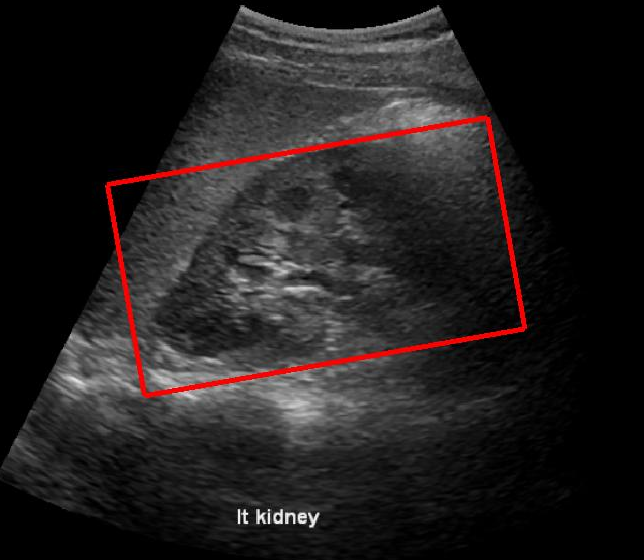

Fig. 3LABEL:sub@subfig:a and LABEL:sub@subfig:b shows a case in which the baseline method was affected by the presence of diaphragm, kidney and liver boundaries creating a texture similar to renal-sinus portion, while CaffeNet had excellent localization. Fig. 3LABEL:sub@subfig:c and LABEL:sub@subfig:d illustrate a case where CaffeNet resulted in over-segmentation containing the diaphragm, clearly illustrating that in limited data problems careful feature-engineering incorporating domain knowledge still carries a lot of relevance. Finally, we achieved a best performance of 86% average detection accuracy using the hybrid approach (Section 3.5). More importantly, the number of failures of the hybrid approach was 3/45, which is 20% better than either of the methods.

(a) Haar

(b) CaffeNet_FA

(c) Haar

(d) CaffeNet_FA

Figure 3: Visual comparison of Baseline Method with CaffeNet Transfer